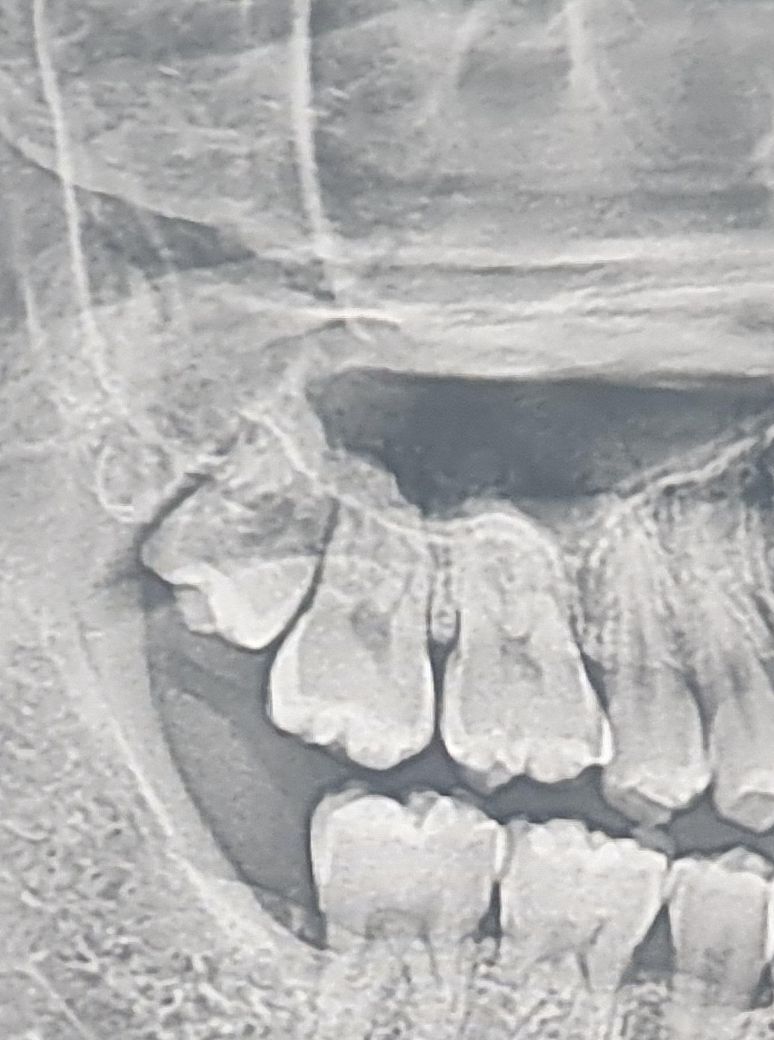

상악 사랑니 천공 가능성 여부에 질문드립니다.

안녕하세요. 다음 주 금요일날 마지막 사랑니 발치하러 갈 예정입니다.

발치 난이도는 상악이 하악보다 훨씬 쉽다고 하셔서 걱정은 안 하고 있었는데

모르는 게 약, 알면 독이라더니 상악동 천공이란게 생길 수 있다고 그러더라고요.

의사 선생님들께서 보시기엔 가능성이 있어보이나요?

• 1번 째 사진

사진으로 봤을 경우에는 사랑니의 뿌리가 상악동에 가까이 있는 것으로 보입니다. 하지만 상악동에 있는 사랑니는 쉽게 나오기 때문에 상악동 천궁까지 유발하지는 않을 것으로 생각됩니다.